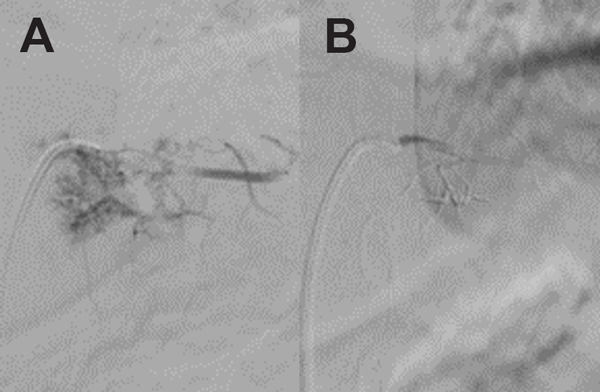

La anatomía patológica informó hemangioma (Figura 4). Se completó el estudio con una angiografía selectiva dorsal (ASD) que reveló una lesión hipervascular con emergencia de la arteria radicular magna de Adamkiewickz a nivel de D7 izquierdo. Se decidió tratamiento mediante embolización tumoral. A los dos meses se efectuó el procedimiento con n-butil-2-cianoacrilato superselectivo embolizando las arterias de los pedículos D8 y D9 bilateral logrando una desvascularización completa de la lesión (Figura 5). A los 4 meses de la cirugía, la RM no mostró progresión de la enfermedad (Figura 6), a los 9 meses, el paciente continúa asintomático, sin déficit motor, sensitivo ni compromiso de esfínteres.

Figura 5. Angiografía digital medular. A) Preembolización. B) Postembolización.